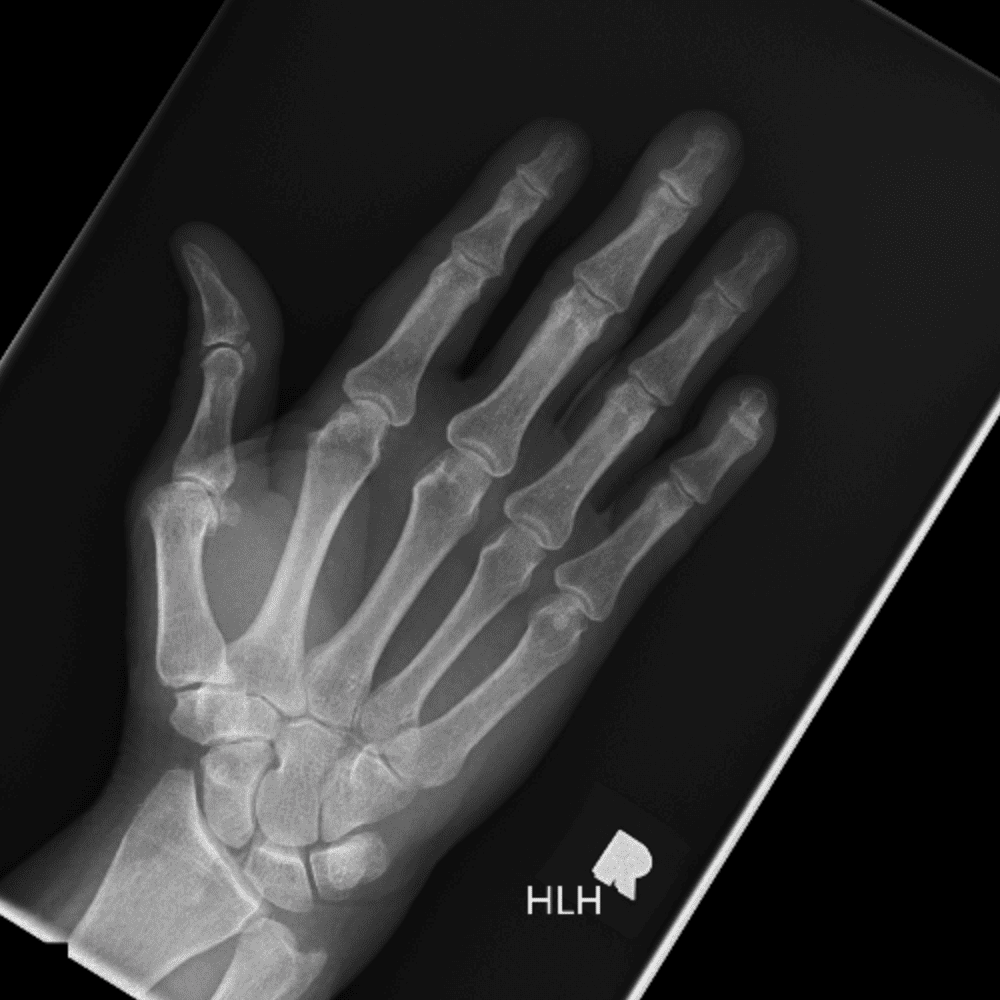

Simuliert den Dienst durch subtile oder schwierige Fälle und einige Normalbefunde.

30 Fälle